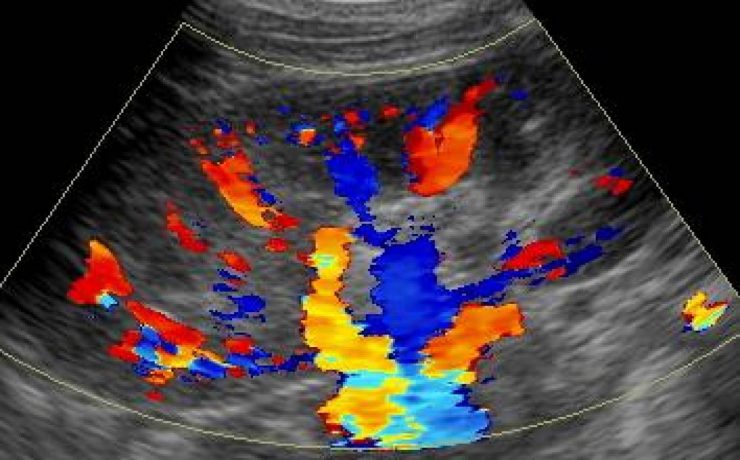

Durante el embarazo y la lactancia, la mama puede verse afectada por una variedad de trastornos únicos y específico, incluyendo trastornos benignos, relacionados con los cambios fisiológicos, inflamatorios, enfermedades infecciosas, papilomatosis juvenil y tumores benignos y malignos. Pacientes con carcinoma de mama asociada al embarazo presentan diagnóstico de neoplasias avanzadas y